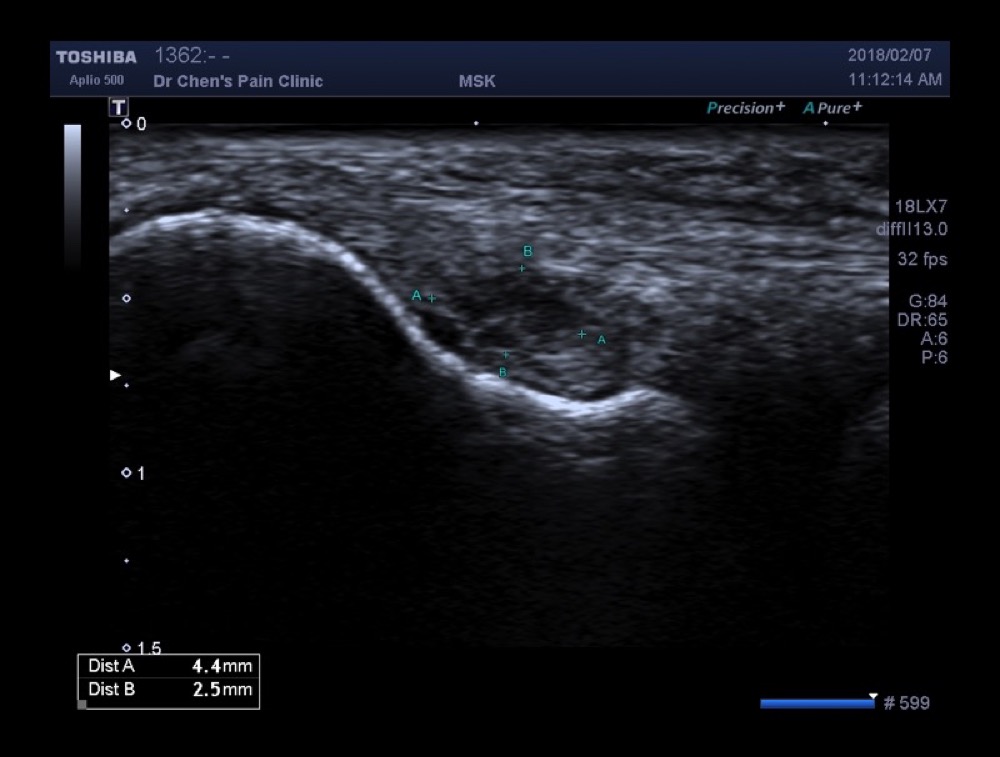

超音波導引治療錄影

在超音波底下,可以藉由注射藥物,發現肌腱斷裂處。